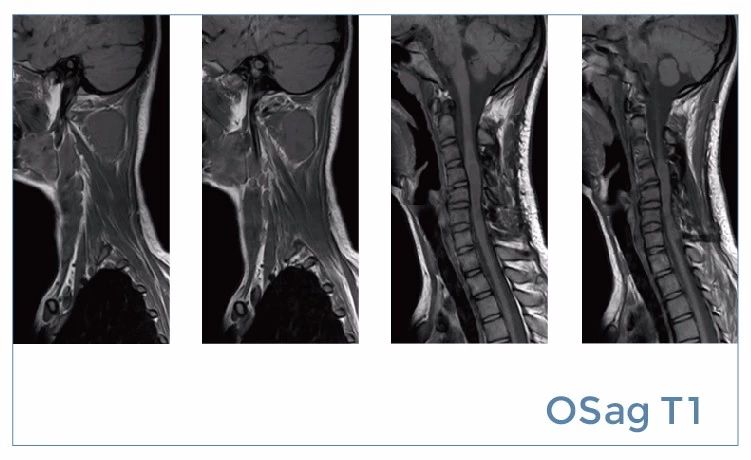

【朗润影像档案】20190816磁共振影像病例结果讨论